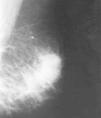

La mastografía mostró una imagen ovalada, densa, con márgenes irregulares en el CSE izquierdo. El diagnóstico fue de lesión sospechosa de malignidad, categoría 4, según el Colegio Americano de Radiología.8 (Fig. 1). En el US la lesión se localizaba entre las 1 y 2 horas de la línea B del radio del reloj, hipoecoica, de márgenes irregulares, de 2,3 * 2 cm en los diámetros anteroposterior y transverso, respectivamente. El estudio Doppler color mostró índices de baja resistencia: 0,44 a 0,48 (Fig. 2). En el gammagrama con sestamibi marcado con tecnecio-99 se observó captación intensa en el sitio de la lesión (Fig. 3). El reporte de la biopsia por aspiración con aguja fina (BAAF) fue de mastitis crónica granulomatosa. La prueba subdérmica de tuberculina fue negativa. En la biopsia incisional se demostraron bacilos ácido alcohol resistentes (BAAR) con la técnica de Zhiel Neelsen y el cultivo del tejido en el medio de Lowenstein-Jensen fue negativo. Para investigar otro foco de Tb se realizó telerradiografía de tórax, la cual fue normal, y además pruebas serológicas como la prueba de ensayo de inmunoabsorbencia de enzimas conjugadas (ELISA) y la prueba de reacción en cadena de polimerasa (PCR), siendo ambas negativas. El tratamiento con isoniacida, rifampicina y pirazinamida a los 3 meses de haberse iniciado causó remisión clínica y los estudios de imagen fueron normales. La paciente continuó el esquema terapéutico hasta completar 6 meses.

Fig. 1. Mamografía en proyección oblicua izquierda. Imagen densa, irregular en el cuadrante superior.